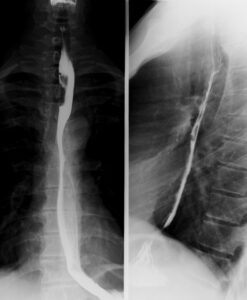

Esophagus with barium swallow